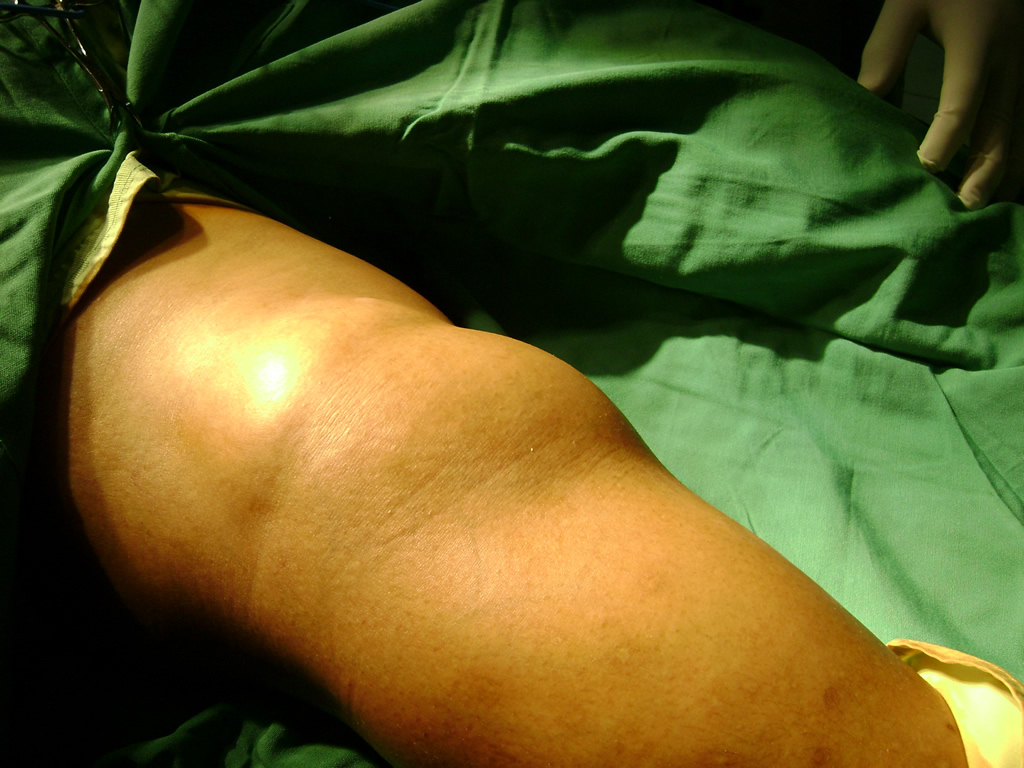

Nos especializamos en brindar tratamiento a las personas que parecen de Quiste de Baker o quiste poplíteo siendo una formación de contenido sinovial producida al debilitarse la membrana sinovial que recubre la articulación de la rodilla.

Este líquido sinovial se acumula en la bursa o bolsa del gastrocnemio-semimembranosa que se comunica con la articulación de la rodilla por una abertura en la superficie posterior y medial de la cápsula articular. El quiste de Baker puede aparecer a cualquier edad incluyendo las etapas tempranas de la vida.

La ruptura de un quiste de Baker origina un cuadro generalmente agudo que se acompaña de tumefacción y dolor del miembro inferior afectado que lleva a impotencia funcional. Muchas veces es confundido con la trombosis venosa profunda por su similitud clínica.